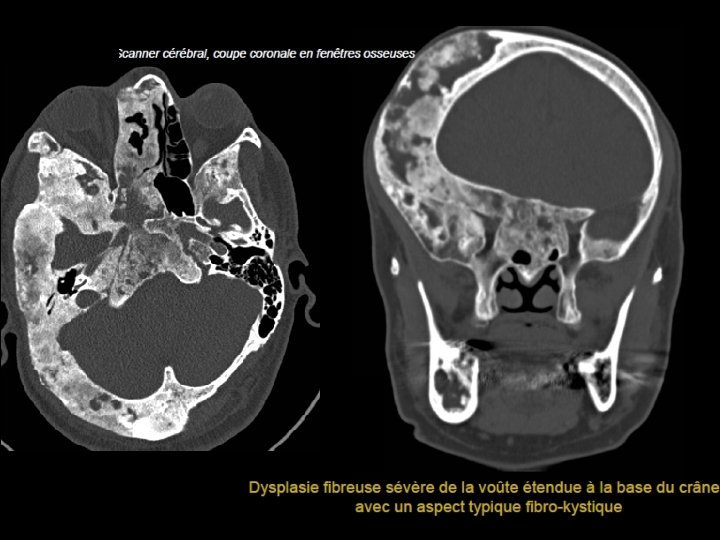

Dysplasie fibreuse • • - Remplacement de l’os normal par du tissu fibreux. Adultes jeunes. Atteinte généralement hémi crânienne. Atteinte focalisée possible: tropisme pour l’os frontal. Dégénérescence maligne rare (0, 4 % à 4% des cas). Association aux kystes anévrismaux 3 types Condensante (opacités en verre dépoli). Kystique Mixte

• Radiographie: lacune ovalaire avec des contours nets et une sclérose périlésionnelle. • Scanner: - Voute épaissie. - Lésion expansive diploïque, kystique. - Table externe: soufflée - Table interne: amincie -Franchissement des sutures -Bilan d’extension aux foramens de la base +++ • IRM -hyposignal T 1 et T 2, rehaussement après injection

Dysplasie fibreuse localisée